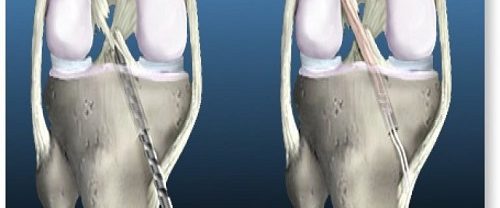

Transfix Tekniği ile Ön Çapraz Bağ Yırtılması ve Tedavi Yöntemleri Transfix Tekniği | Ön çapraz bağ yırtılması, genellikle spor yaralanmaları veya ani dönme hareketleri sonucu ortaya çıkan bir durumdur. Bu yırtık, dizin stabilitesini etkileyebilir ve günlük aktivitelerde ve spor yaparken ağrı ve kısıtlılığa neden olabilir. Ön çapraz bağ yırtılması olan birçok kişi için cerrahi müdahale gerekebilir.…